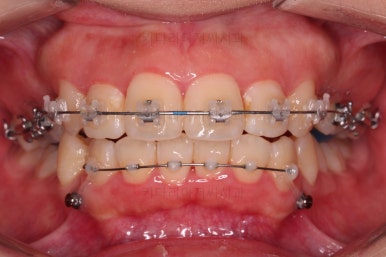

부산무턱교정치과 초진 시 입안의 모습입니다.

전반적으로 치열이 삐뚤고요. 아랫니가 윗니보다 뒤쪽으로 많이 가려져 있죠.

그래서 앞에서 봤을 때 아래 앞니가 거의 보이지 않는 상태인데요.

이런 교합을 "과개교합"이라고 표현합니다.

전반적인 교합, 치열, 과개교합, 튀어나와 보이는 앞니 등을 개선해줘야겠네요.